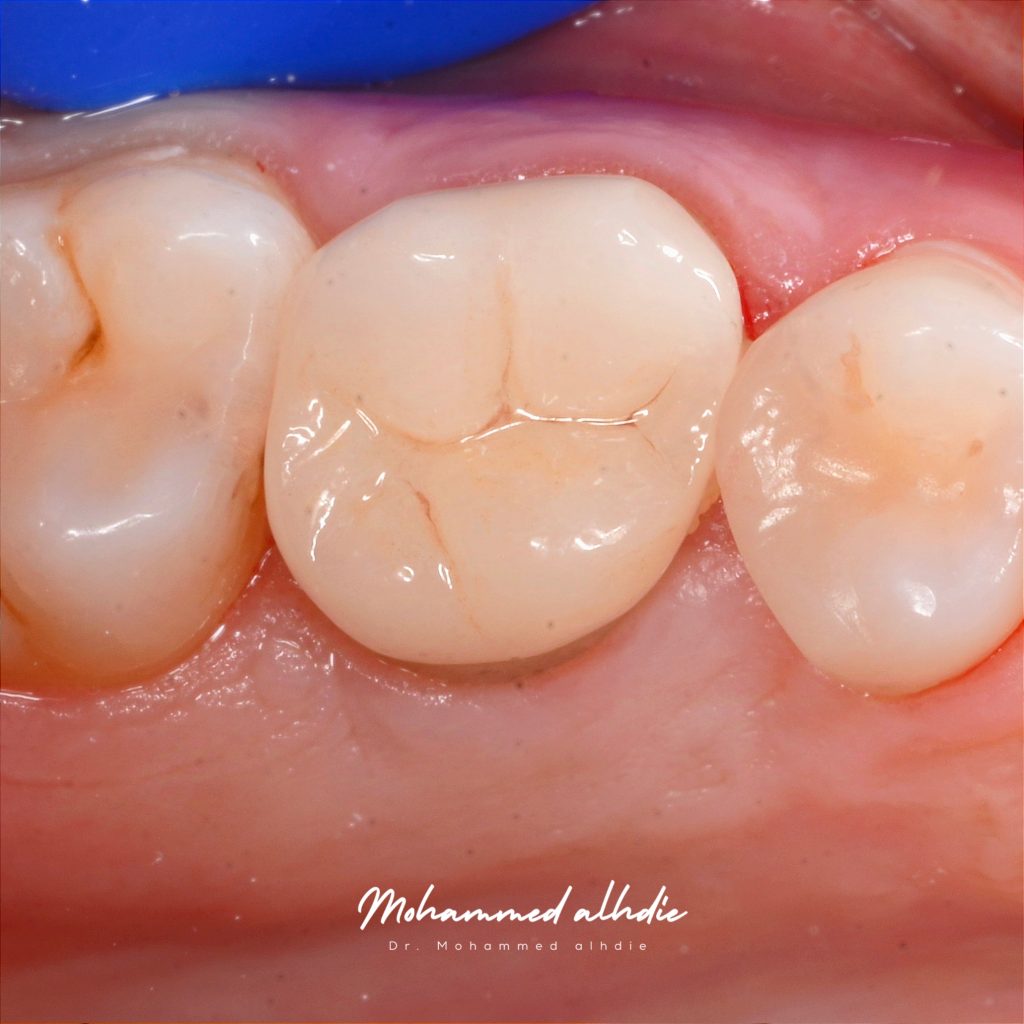

Finally follow up after 4 month and we see gingiva is healthy

أخيرا تم استعادة الحياة لهذه السن

Final result and directly result

Another view Follow up after 4 month

Follow up after 4 month